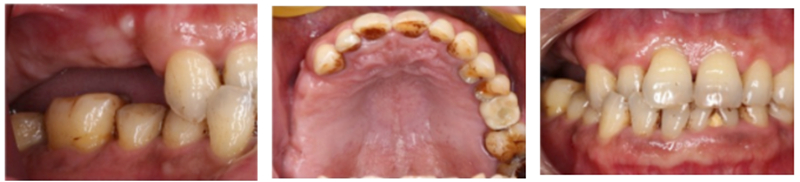

檢查:患者14、15、16、17缺失,無紅腫潰瘍,牙齦情況良好,口腔衛(wèi)生狀況良好。

診斷:14、15、16、17缺失